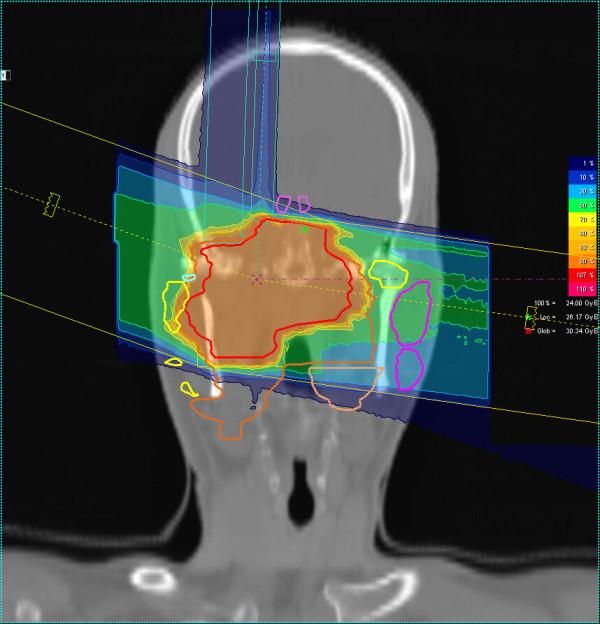

COSMIC is a prospective phase II trial of IMRT (25 × 2 Gy) and carbon ion boost (8 × 3 GyE). Primary endpoint is mucositis CTC°III, secondary endpoints are local control, progression-free survival, and toxicity. Evaluation of disease response is carried out according to the Response Evaluation Criteria in Solid Tumors (RECIST); toxicity is assessed using NCI CTC v 3.0.

COSMIC 是一项前瞻性 II 期 IMRT(25×2Gy)和碳离子推量递增(8×3GyE)的试验。主要终点是粘膜炎 CTC°III,次要终点是局部控制、无进展生存期和毒性。根据实体瘤反应评估标准(RECIST)评估疾病反应;使用 NCI CTC v 3.0 评估毒性。